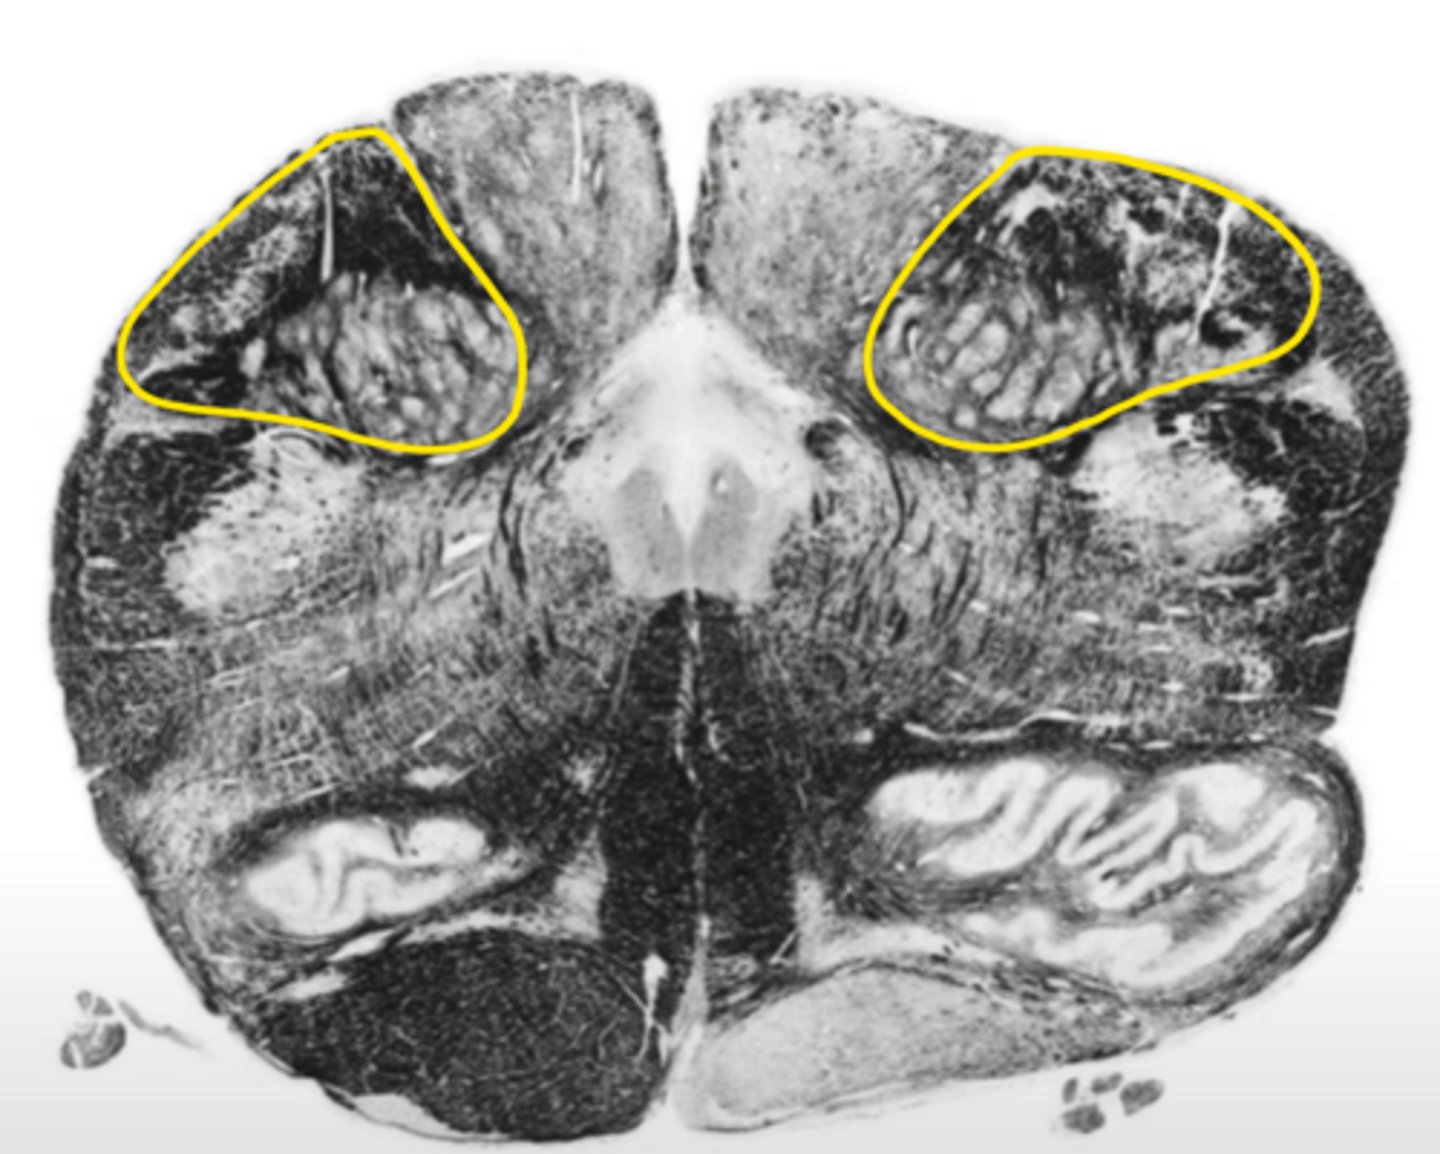

closed medulla

ID the brainstem level